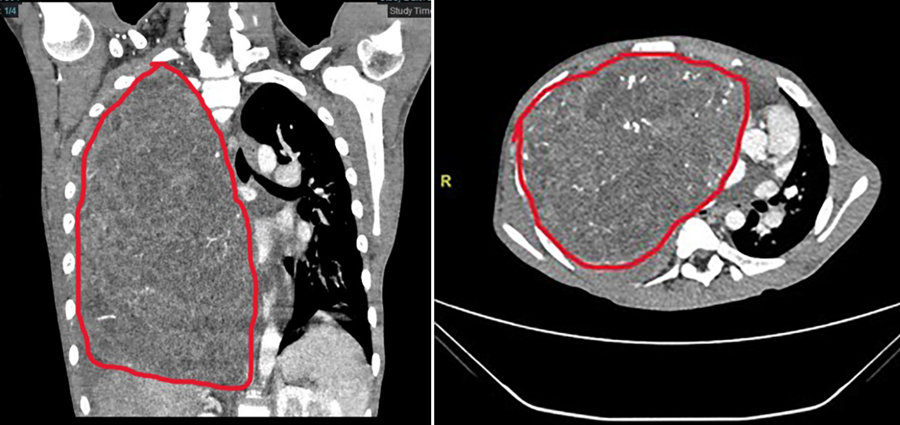

小宇体内的纵膈肿瘤尺寸达29×27×15厘米,长满右侧胸腔并延伸到左侧,将心脏从正常位置挤压到左侧胸壁边缘,并严重压迫周边脏器、影响心肺功能。更棘手的是,肿瘤血供丰富,与周围组织粘在一起,手术切除风险极高,极易引发致命性大出血。

手术当日,麻醉科副主任医师郭东东及团队全程严密护航,丁建勇教授和复旦儿科心胸外科张文波副主任医师密切配合,精细操作,逐层剥离,成功将肿瘤完整切除,术中出血不到100毫升。切下的肿瘤重达7斤3两,超过了成年人头颅大小。术后小宇心肺压迫即刻解除,顺利转入康复治疗,并于近日顺利出院。